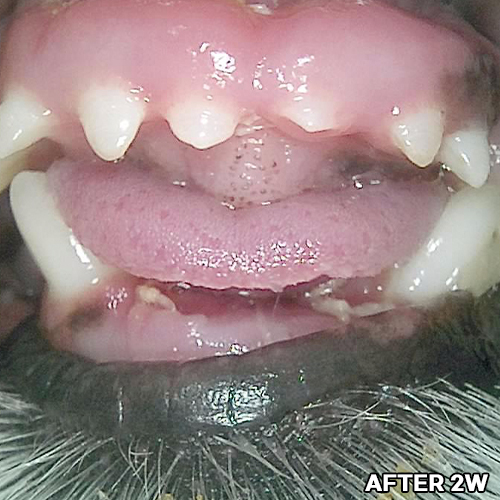

[최소침습적 발치 후 2주 경과]

샘플